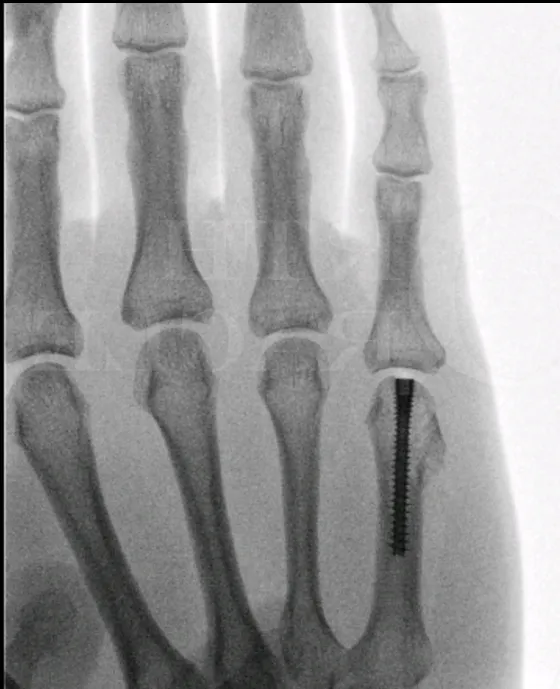

- Stap 3: Operatie: Als een vingerbreuk niet goed uitgelijnd kan worden of als het een open breuk betreft, is een operatie aangewezen. Ook bij een gewrichtsbreuk (fractuur die door een gewricht loopt) zal men laagdrempelig opereren om het gewricht zo egaal mogelijk te herstellen en latere artrose te voorkomen. Tijdens de operatie zet de chirurg de botstukken in de juiste positie en bevestigt ze met metalen pinnen, schroefjes of mini-plaatjes. Voor fracturen in het topje van de vinger (nagelkootje) gebruikt men vaak dunne pennetjes die gedurende enkele weken door de huid steken. Voor midden- of grondkootjes (middenste en onderste vingerbotjes) kan een plaatje met schroefjes nodig zijn bij complexe fracturen. Na de ingreep wordt de vinger ingespalkt. Later begint men voorzichtig met bewegingsoefeningen onder begeleiding (om te voorkomen dat de geopereerde vinger vast komt te zitten).